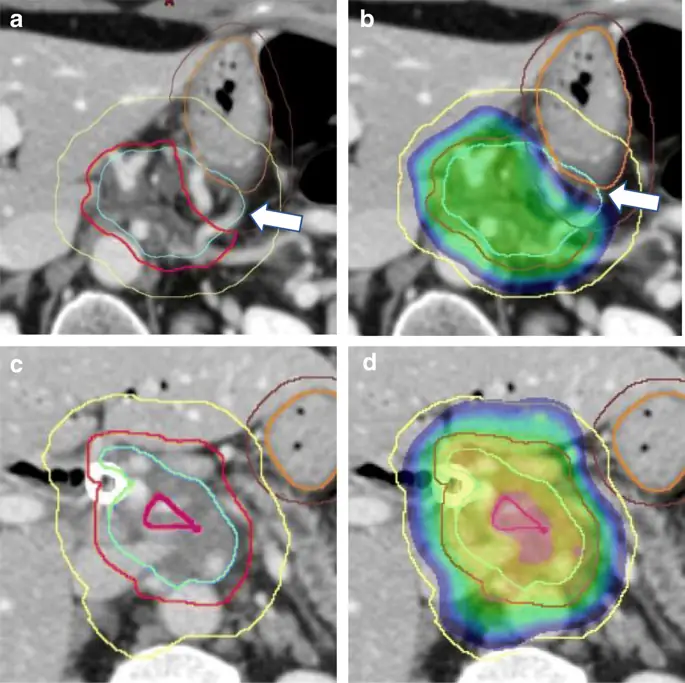

Другим концептуальным изменением, которое способствовало бы увеличению дозы, является отказ от цели однородности дозы с объемом лечения при планировании опухоли (PTV). Однородность дозы в качестве цели планирования в значительной степени перенесена из более традиционных подходов планирования. Когда на больших полях лечения находились как мишень, так и органы, подверженные риску, горячие точки в облученном объеме были нежелательны. Однако, когда планируемый объем лечения мал и ограничен опухолью, исключая все чувствительные нормальные структуры, горячая точка в этом объеме лечения не оказывает вредного воздействия. Напротив, наличие горячей точки может улучшить конформность распределения высокой дозы, что позволит увеличить дозу. Важно отметить, что центр опухоли обычно более гипоксичен, чем периферия, и, следовательно, более радиорезистентен. Горячая точка в более радиорезистентной части опухоли будет только полезна. Таким образом, наша новая стратегия планирования лечения представляет собой трехэтапный подход: (1) охватить как можно большую часть опухоли абляционной дозой, (2) расположить супраабляционные горячие точки в центре и (3) ограничить области, непосредственно прилегающие к Желудочно-кишечный тракт в безопасных дозах применяется при обычной лучевой терапии (рис. 1).

Контурирование и оценка плана. a и c Имитационные КТ, показывающие микроскопическую дозу GTV (голубой), высокой дозы PTV (красный) и PTV (желтый), а также желудок (оранжевый) с вырезанной структурой (коричневый), используемый для обеспечения исключения желудка из высокой дозы PTV как показывает белая стрелка. b и d Распределение дозы с наименьшей отображаемой дозой, установленной на критическую максимальную дозу дозы для желудка (60 Гр). Белая стрелка указывает на то, что линия изодозы 60Gy удалена от поверхности желудка, что было достигнуто путем создания PRV (не показано). c и d Пример, который включает дополнительную сверхвысокую дозу PTV (пурпурный)